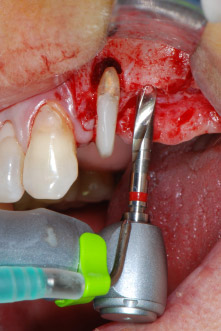

En primer lugar, en un intento por gestionar el problema endo-periodontal, el resto de la superficie radicular se desbridó con cuidado con un equipo piezoeléctrico (Piezomed de W&H, utilizado con el inserto S1 con forma de espátula, concebido en un principio para la erosión de la pared lateral del seno) (figura 4). A continuación, el ápice se erosionó con el mismo instrumento para eliminar el tejido apical infectado residual y reducir las posibles ramificaciones accesorias del canal radicular (apicectomía) (figura 5). No fue necesario realizar un retrorellleno, puesto que la obturación ortógrada se acababa de revisar.

Antes de colocar el implante, el tejido infectado del hueso alveolar ubicado en el lugar del implante y alrededor de los dientes del pilar se retiró con un inserto concebido en un principio para modelar huesos y recoger virutas óseas: Piezomed y el inserto B5 (figuras 6 y 7).